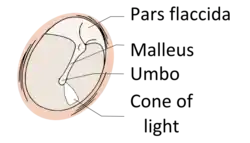

The eardrum is divided into two general regions: the pars flaccida and the pars tensa.[3] The relatively fragile pars flaccida lies above the lateral process of the malleus between the Notch of Rivinus and the anterior and posterior malleal folds. Consisting of two layers and appearing slightly pinkish in hue, it is associated with Eustachian tube dysfunction and cholesteatomas.[4]

The larger pars tensa consists of three layers: skin, fibrous tissue, and mucosa. Its thick periphery forms a fibrocartilaginous ring called the annulus tympanicus or Gerlach's ligament.[5] while the central umbo tents inward at the level of the tip of malleus. The middle fibrous layer, containing radial, circular, and parabolic fibers, encloses the handle of malleus. Though comparatively robust, the pars tensa is the region more commonly associated with perforations.[6]

The manubrium (Latin: handle) of the malleus is firmly attached to the medial surface of the membrane as far as its center, drawing it toward the tympanic cavity. The lateral surface of the membrane is thus concave. The most depressed aspect of this concavity is termed the umbo (Latin: shield boss).[7]

When the eardrum is illuminated during a medical examination, a cone of light radiates from the tip of the malleus to the periphery in the anteroinferior quadrant, this is what is known clinically as 5 o'clock.